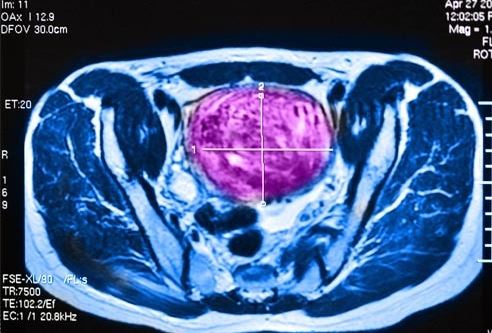

11 常規的骨盆檢查可讓醫生髮現中等或較大的 肌瘤。

超聲波 可顯示 肌瘤 的大小和位置。患子宮肌瘤 想要懷孕的女性

可進行 子宮輸卵管 照影片 來觀測 子宮和輸卵管 情況, 也可防患於未然。